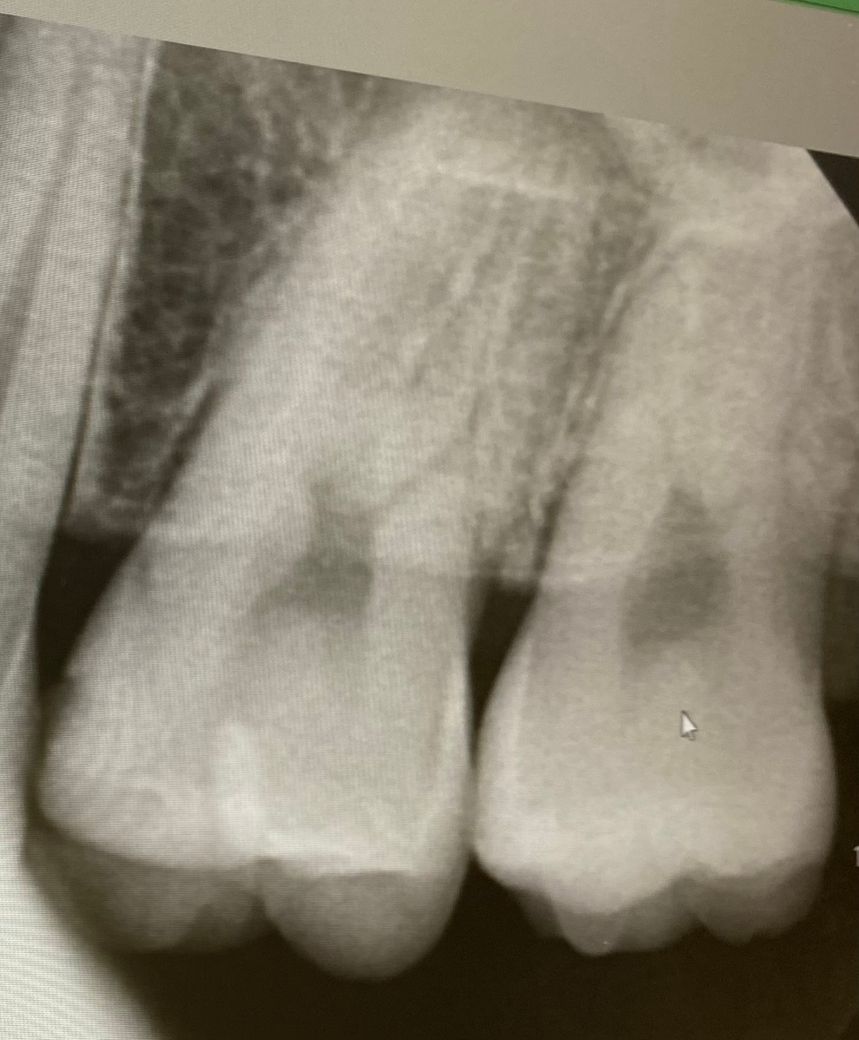

1번 치과는 왼쪽 위 4번째 안쪽면에 인접면 충치

왼쪽 위 2번째 어금니 레진속 2차 충치로

인레이 개당 35만 레진 15만원 씩 진료 받았습니다

육안상으로보면 치아 사이에 충치가 잇는거 같습니다. 관리를 잘하시면 진행이 안되겟지만 관리가 안되면 충치 진행이 빨라져서 신경치료를 해야될수도 잇으니 저라면 미리 치료를 하라고 권유할것같습니다 .

육안으로 봤을 경우에는 인접면에 충치가 있는 것으로 보이긴 합니다. 하지만 엑스레이 사진상으로 크게 보이지 않기 때문에 관리를 해서 사용할 수 있는 경우도 있습니다. 충치가 더 커지는 것을 방지하기 위해 예방적으로 치료를 하고자 한다면 치료가 필요할 수 있으며 그렇지 않다면 관리를 하면서 상태를 지켜볼 수 있습니다.